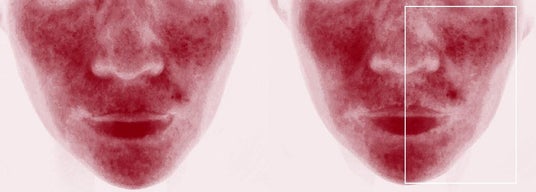

症例2

レーザー治療直後 半顔(囲み内)にAIR(アイル)後

上下ともに:機器治療後、半顔だけにAIR(アイル)を20分適用し、前後にヘモグロビン強調画像を撮り検証した。上の症例写真は、右側(向かって左/囲み内)の赤みがより減少、下の写真は、左側の赤み(向かって右/囲み内)がより減少しており、どちらも赤みがより減少したほうがAIR(アイル)を適用した側だった(画像提供:奥謙太郎院長)。

研究デザイン

15名の患者を対象に、マイクロニードル RFもしくはピコ秒アレクサンドライトレーザーを照射後、全顔にフェイシャルパックを行い、半顔のみ微細水粒子「AIR(アイル)」を20分間適用。「AIR」適用側はランダムに割り付け。機器治療前後とフェイシャルパック後、ヘモグロビン強調画像を撮影し、独立評価者が「AIR」適応前後のヘモグロビン強調画像を比較しAIR適応側を正しく同定できるかを検証した。「AIR(アイル)」適用側が正しく同定されたのは15症例中13症例(86.7%)であった。